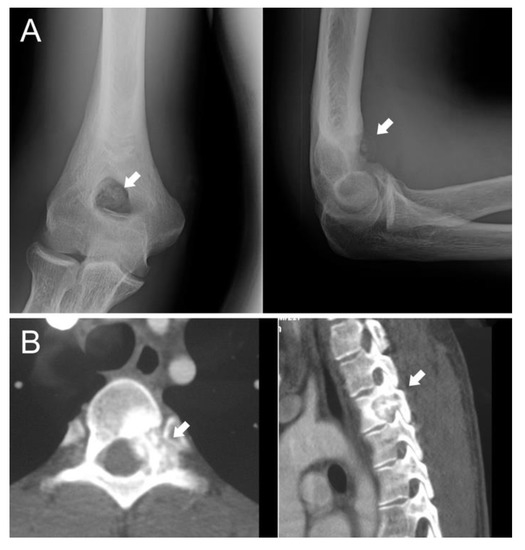

In the presented series, a proximity to nerves was the main indication for surgery; indeed, thermoablation can cause them damage. Additionally, tumor size and shape have to be considered: an irregular shape can be a contraindication for minimally invasive treatment, such as a risk of fracture. In case 3, we preferred to surgically remove the tumor and then to fill the cavity with a homograft to decrease the risk of great trochanter avulsion (Figure 2). Localization should also be considered in the indications for surgery.

When OBLs are located in the limbs, an intralesional approach can be considered the best-choice treatment, although, if the lesion is small, thermoablation has to be carefully assessed. Surgery is necessary in cases with a risk of fracture (case 3; Figure 4) because bone filling is required. Resection can also be considered for OBLs located near neurovascular bundles.

Figure 4. Case 3, a male patient with OBL of the right trochanter; on the upper image, the X-ray shows a quite well-defined osteolytic lesion (white arrows); on the lower image, the related MRI highlights the important oedema surrounding the OBL. The indication for surgery was based on the risk of a fracture due to both eventual RF thermoablation and the action of pelvic-trochanteric muscles.